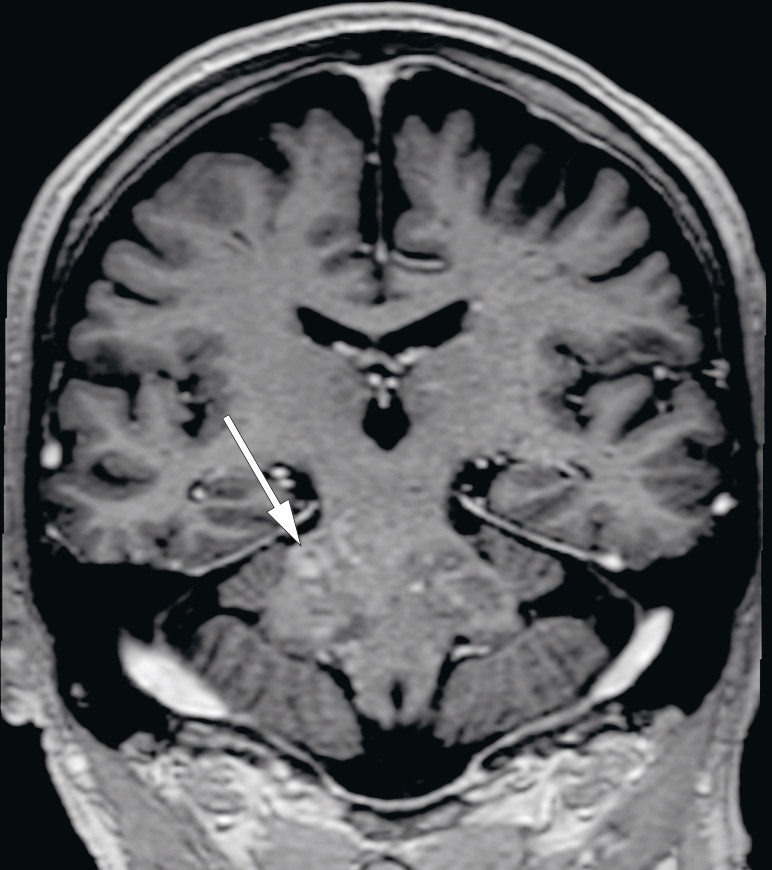

MR av hodet tatt en måned etter utskrivelse viste multiple lesjoner med høyt signal på T2-vektet serie og FLAIR (fluid-attenuated inversion recovery) i den forlengede marg, hjernebroen, midtre lillehjernestilk, venstre lillehjernehemisfære, midthjernen på venstre side og i basalganglieregionen på venstre side (figur 1). Det var også en liten lesjon i øvre del av ryggmargen i nivå C1 på venstre side samt subkortikalt parietalt på venstre side. Etter injeksjon av kontrastmiddel var det varierende grad av punktformet og stripeformet kontrastladning, som stedvis var konfluerende (figur 2). MR-angiografi av hjernearterier viste en liten stenose i høyre bakre hjernearterie, som ble oppfattet som aterosklerotisk betinget. Det var ellers normale arterier. En var på dette tidspunktet usikker på hva forandringene representerte, og pasienten ble innlagt på nevrologisk avdeling samme dag for utredning.

Pasienten utviklet tre uker etter innleggelsen markant klinisk forverring med økende og betydelige gangvansker, økende dysartri og psykomotorisk latens. Hjernelesjonene lå ikke lett tilgjengelig for biopsi. Radiologisk ble CLIPPERS-syndrom (chronic lymphocytic inflammation with pontine perivascular enhancement responsive to steroids) foreslått som differensialdiagnose med tanke på MR-undersøkelsen hvor man fant kontrastladninger i hjernestammen på 3D-T1-serien. Sammenholdt med resultatene av de kliniske undersøkelsene samt mangelen på alternativ forklaring ble CLIPPERS-diagnosen ansett som den mest sannsynlige.

Syndromet som kalles CLIPPERS – chronic lymphocytic inflammation with pontine perivascular enhancement responsive to steroids – er en relativt nylig definert inflammasjonstilstand i sentralnervesystemet som hovedsakelig rammer hjernestammen, særlig hjernebroen. Tilstanden ble først beskrevet i 2010 (1) som en form for hjernestammeencefalitt lokalisert i hjernebroen, kjennetegnet av predominant T-celle-patologi og av at den responderer på immunsuppresjon med glukokortikoider. Symptomene er hovedsakelig knyttet til involvering av hjernestammen, spesielt gangataksi og dobbeltsyn. Andre symptomer inkluderer dysartri, endret sensibilitet og parestesier i ansiktet, svimmelhet, nystagmus, spastiske parapareser og pseudobulbær affekt. MR hos vår pasient viste karakteristisk mønster i form av perivaskulær kontrastladning i hjernebroen og andre deler av bakhjernen (1).

MR-funn er karakteristiske og spiller en avgjørende rolle i diagnostiseringen (3). Karakteristiske trekk er homogene, kontrastladende lesjoner større enn 3 mm i diameter, uten masseeffekt predominerende i hjernebroen og lillehjernen, med tydelig reduksjon av kontrastladning etter steroidbehandling. Lesjoner kan strekke seg til nærliggende sentralnervesystemstrukturer, kaudalt til den forlengede marg og ryggmargen, samt til supratentoriale regioner som talamus, capsula interna, basalgangliene, hjernebjelken og hvit substans (1, 3, 8).